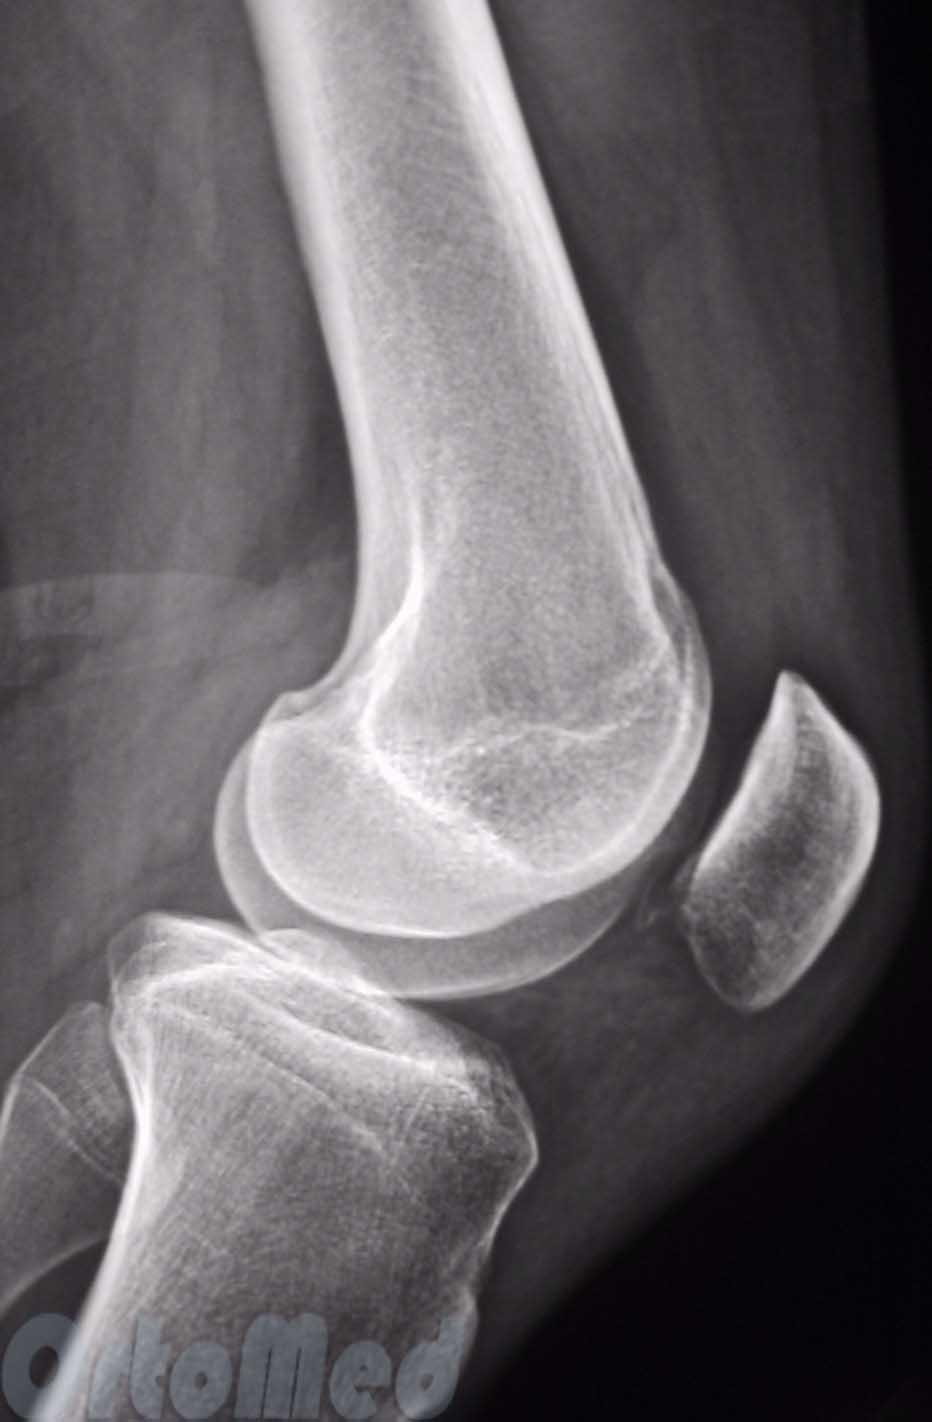

Сверху – боковая рентгенограмма, снизу – аксиальная, на которой видно нормальное взаимоотношение надколенника и бедренной кости

Бывает гиперпрессия коленной чашечки, то есть повышенное давление на суставную фасетку – латеральная гиперпрессия, то есть повышенное давление на наружный мыщелок бедренной кости, медиальная гиперпрессия, то есть повышенное давление на внутренний мыщелок бедренной кости. При латеральной гиперпрессии надколенник давит на наружную фасетку, при ещё большем смещении – появляется подвывих надколенника, при полном смещении – вывих.

Слева – подвывих надколенника, тенденция к смещению кнаружи; справа – вывих надколенника